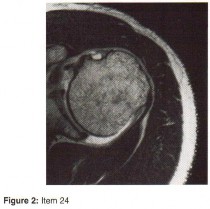

Question 24

A patient presents with acute knee swelling following trauma. MRI scans (T1 and T2-weighted) are shown. The layering effect seen within the joint space is most strongly associated with which of the following underlying injuries?

Explanation

Correct Answer: Intra-articular fracture

The MRI shows lipohemarthrosis, characterized by layering of fat (superior, high signal on T1), serum (central, low signal), and red blood cells (inferior, low signal). This finding is highly indicative of an intra-articular fracture, which allows marrow fat to escape into the joint space.